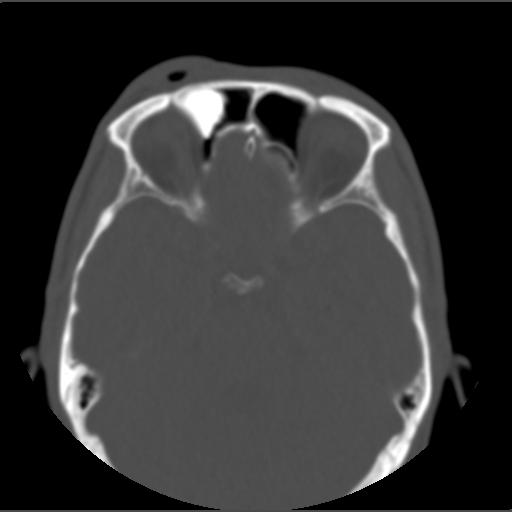

m49y外伤常规ct发现筛额窦右侧高密度块影 。

右侧额筛都内致密性高密度影,余骨皮质未见明显异常改变,右额皮下血肿伴少许积气,我想是致密影是骨瘤.

右侧额筛都内致密性高密度影,境界清楚,余骨皮质未见明显异常改变,符合骨瘤表现

右侧额筛都内致密性高密度影,境界清楚,余骨皮质未见明显异常改变,考虑额筛窦内生性骨瘤.

颅面部骨瘤一般密度致密,多发额骨及鼻窦腔壁,呈扁丘样改变.边界清楚,大部分密度均一.

1、致密型骨瘤。2、右额部头皮挫裂伤。

右额窦至密性骨瘤,右额骨皮下软组织挫伤拌积气.